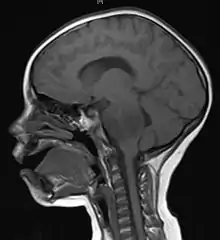

![]() انبثاث الورم الدماغي في نصف الكرة الدماغية الأيمن بسبب سرطان الرئة يظهر بالتصوير بالرنين المغناطيسي الموزون بT1 مع التباين داخل الوريد. انبثاث الورم الدماغي في نصف الكرة الدماغية الأيمن بسبب سرطان الرئة يظهر بالتصوير بالرنين المغناطيسي الموزون بT1 مع التباين داخل الوريد. | |

وفي الغالب، تظهر أورام المخ الرئيسية (الحقيقية) في الحفرة القحفية الخلفية لدى الأطفال وفي الثلثين الأماميين من نصفي الكرة المخية لدى البالغين، رغم أنها يمكن أن تؤثر على أي جزء من المخ.